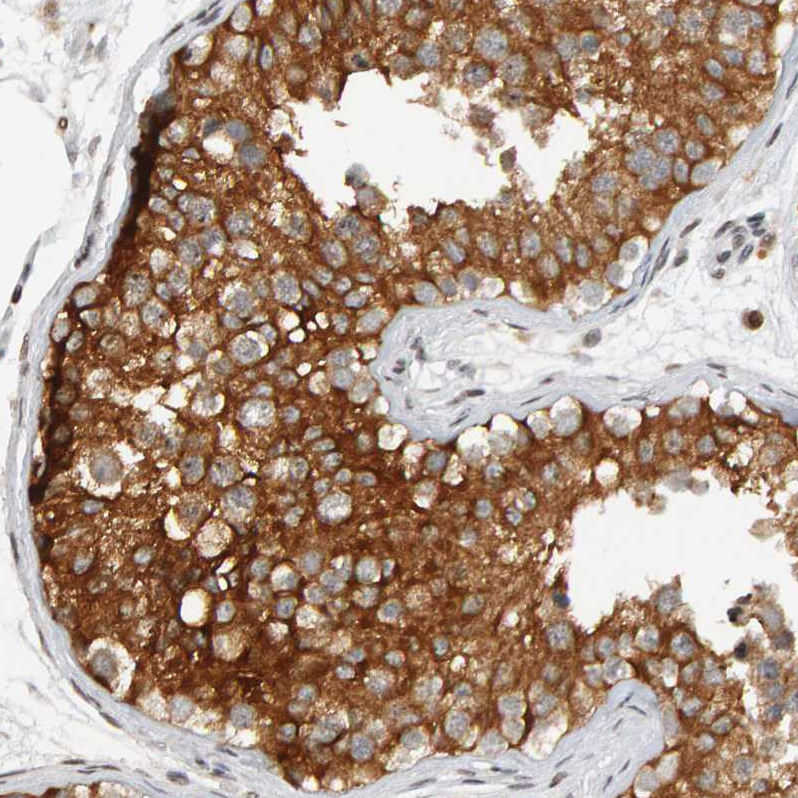

Immunohistochemical staining of human liver shows strong granular cytoplasmic positivity in hepatocytes.